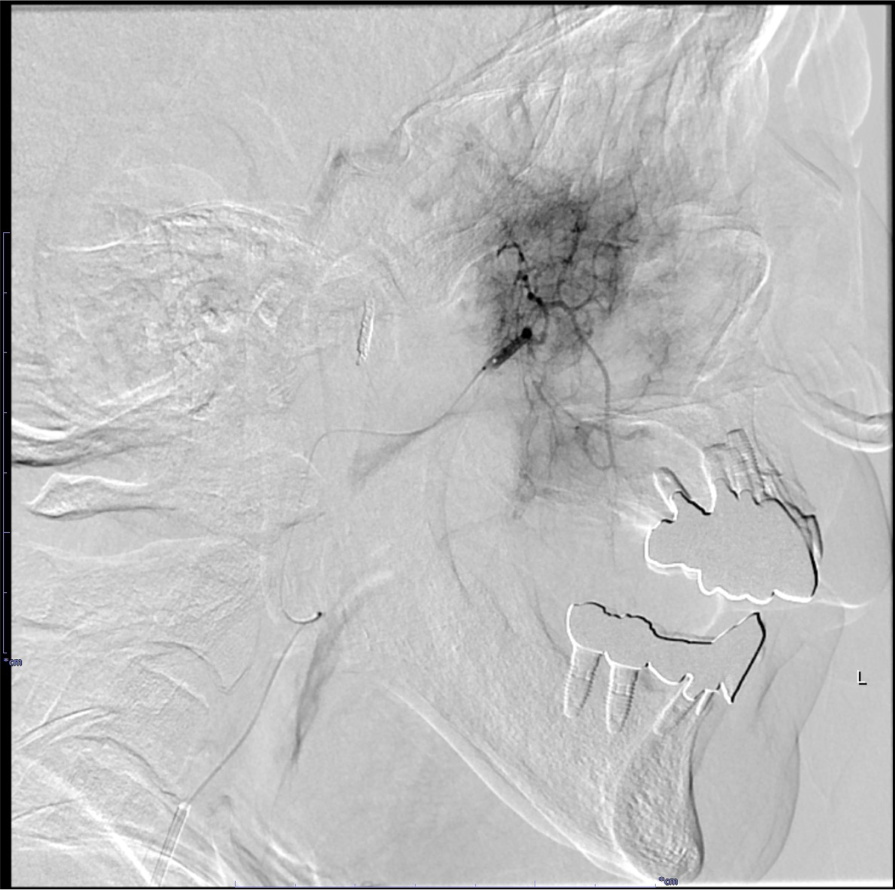

RADPLATは大量シスプラチンの超選択的動注化学療法と放射線治療の同時併用療法であり、局所制御の向上と臓器機能温存を期待できる。超選択的動注化学療法で癌の根治を目指す上で、腫瘍の進展範囲や栄養血管の同定、また周囲の重要構造物との関係やアクセスルートなど詳細な術前評価が不可欠であり、造影CTで解剖学的構造物を正確に描出することが求められる。

当院では撮像されたCT画像を元に3D画像解析システム「SYNAPSE VINCENT」を使用して治療対象となる血管を抽出し、ワークステーション上で支援画像を作成している。これにより直感的な解剖の理解を得られるだけでなく、放射線技師や看護師など手技に関わるスタッフと事前に情報共有することが容易になり、これもまた治療の有効性や安全性を高めることに寄与する。

画像再構成は腫瘍の位置や血管走行を詳細に評価するため、0.5mmにスライス厚を設定する。各動脈、腫瘍を色分けしたVR像なども血管造影の際の支援画像として重要である。